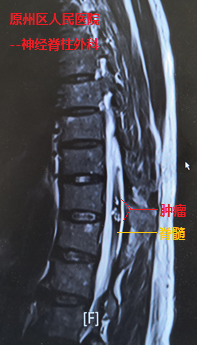

經檢查發現,在史伯伯的胸椎脊髓內,長有信號混雜不均的血管性腫瘤,并隨著腫瘤出血膨脹,幾乎占據了整個脊髓,導致患者一側下肢近遠端肌力完全喪失(0級),另一側下肢也僅能勉強移動(2-3級)。當地醫院神經脊柱外科主任萬欣龍判斷,史伯伯得的可能是脊髓髓內的海綿狀血管瘤并發出血卒中,如若不進行手術,隨著腫瘤出血后脊髓水腫的加重,病情將進一步惡化。

我院神經外科援寧隊員鄭小斌在查看患者并詳細閱片后,組織了疑難病例討論,考慮到患者血管性腫瘤體積大,且生長時間長達十余年,導致該腫瘤與周圍脊髓組織的血供情況復雜,最終決定采用顯微鏡下經脊髓外側溝切開脊髓并暴露腫瘤。鄭小斌介紹,術中對腫瘤與脊髓邊界的分離是手術的關鍵,加上患者脊髓功能受損嚴重,手術操作既要精細輕柔,也需連貫穩定。經過近2個小時不間斷的顯微鏡下操作,腫瘤順利從脊髓內切除,周圍的脊髓的正常結構得到保護。鑒于腫瘤體積大,出血后脊髓水腫嚴重,同期給予行脊柱椎板切除減壓手術,并進行內固定手術加強脊柱的穩定性,手術順利完成。

鄭小斌博士介紹,該脊髓血管性腫瘤由于體積較大,并且生長時間久,瘤周及脊髓表面的血管出現反應性增生,尋找合適的脊髓切開位置并暴露腫瘤,同時保護好脊髓的正常血供與靜脈引流系統,是顯微鏡下操作首先需要注意的。該血管性腫瘤呈分塊狀,除了需要高倍顯微鏡下的操作,如何在盡可能小的脊髓切開范圍,全部摘除腫瘤,并保護好脊髓的血供與靜脈引流系統,最大化保留脊髓的殘存功能,是手術操作的原則。